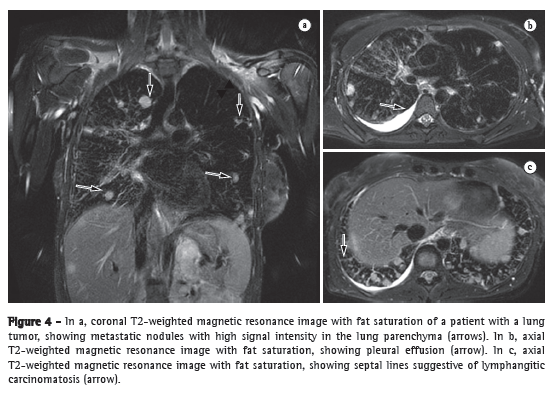

Because it provides higher efficacy in TNM stage determinations than do conventional staging methods, integrated PET/CT seems to be a first-line lung cancer staging tool. However, MRI has come to play an increasingly more important role in this setting. Figure 4 shows the ability of an MRI scan to clearly depict local metastases of a lung tumor. It has been reported that PET/CT fails to reveal microscopic metastases in approximately 20% of patients undergoing surgical therapy.(12) Previous studies have demonstrated that whole-body MRI provides acceptable accuracy, and that its efficacy in lung cancer staging is comparable to that of PET/CT.(13) Each of those two imaging modalities has been shown to have its advantages,(12) whole-body MRI being better for detecting brain and liver metastases, whereas PET/CT is better for detecting lymph node and soft-tissue metastases. For the evaluation of areas that have been submitted to radiation therapy, one promising technique is diffusion.(12) Whole-body MRI with diffusion-weighted imaging can be used for the assessment of the M (metastasis) stage in NSCLC patients and has been shown to be as accurate as is PET/CT.(14)